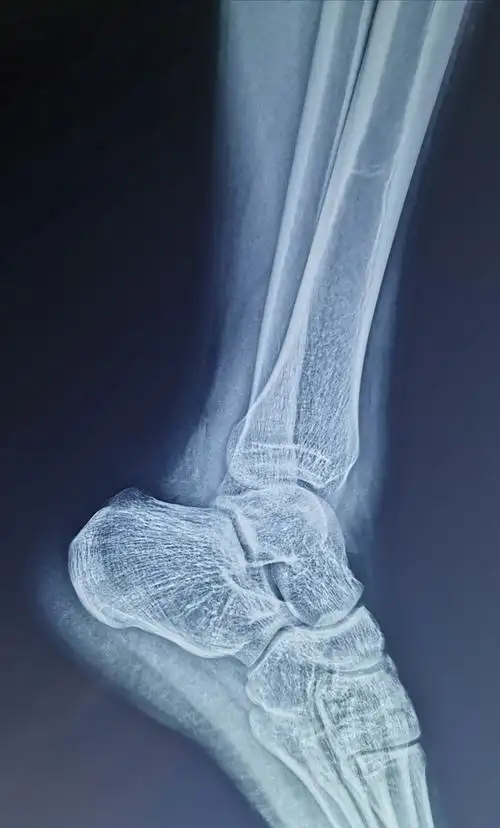

外踝撕脱性骨折 - 骨科 -丁香园论坛

右外踝撕脱性骨折,保守治疗,麻烦帮忙看看多久可以恢复,会不会有后遗